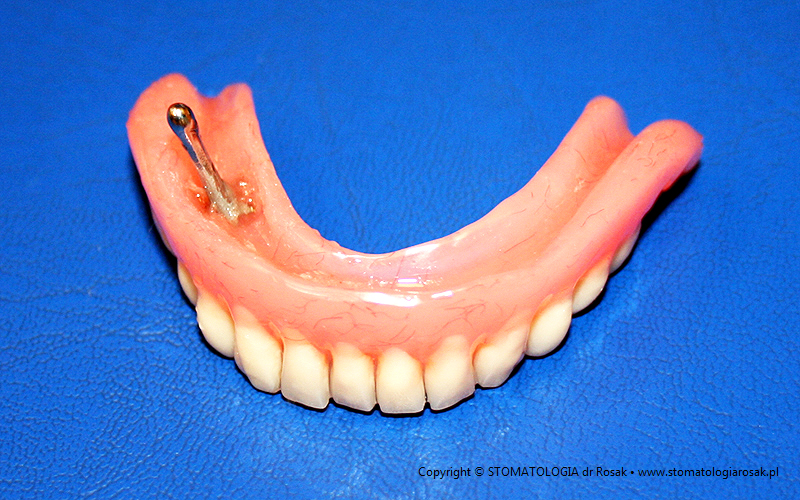

10. Pacjentka 55 lat – zgłosiła się celem usunięcia ostatniego korzenia w żuchwie. Ze względu na rozległe zaniki wyrostka zębodołowego i dobry stan korzenia zęba wykonaliśmy leczenie zachowawcze i precyzyjny element retencyjny w postaci zatrzasku kulowego, który stabilizuje protezę. Założeniem, ze względu na duże obciążenie całą protezą 14-zębową, było utrzymanie pracy przez okres roku… przy bezzębiu każda próba zwiększenia stabilizacji jest na wagę złota, zwłaszcza w żuchwie (na dole), stąd rozwój implantoprotetyki – mocowanie protezy na implantowanych śrubach.

|

| 10a. Zatrzask kulowy na resztkowym korzeniu |

10b. Zbliżenie zatrzasku kulowego |

11. Ta sama pacjentka po okresie, bagatela, 3,5 roku. Tym razem ząb trzeba już było usunąć.

Mieliśmy jednak do wykorzystania jeszcze zębodół po nim i dlatego też zrobiliśmy tzw. wkład dozębodołowy

… proteza dalej ma zadowalającą stabilizację.

| 11a. Stan po usuniętym korzeniu zęba |

11b. Widok strony dośluzówkowej protezy z zamontowanym

już gotowym wkładem dozębodołowym |